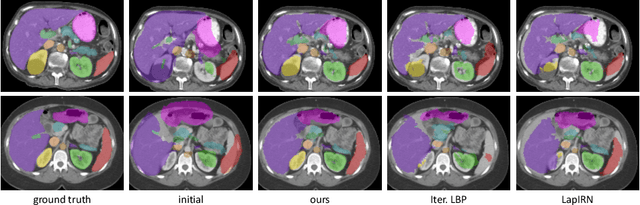

Abstract:State-of-the-art deep learning-based registration methods employ three different learning strategies: supervised learning, which requires costly manual annotations, unsupervised learning, which heavily relies on hand-crafted similarity metrics designed by domain experts, or learning from synthetic data, which introduces a domain shift. To overcome the limitations of these strategies, we propose a novel self-supervised learning paradigm for unsupervised registration, relying on self-training. Our idea is based on two key insights. Feature-based differentiable optimizers 1) perform reasonable registration even from random features and 2) stabilize the training of the preceding feature extraction network on noisy labels. Consequently, we propose cyclical self-training, where pseudo labels are initialized as the displacement fields inferred from random features and cyclically updated based on more and more expressive features from the learning feature extractor, yielding a self-reinforcement effect. We evaluate the method for abdomen and lung registration, consistently surpassing metric-based supervision and outperforming diverse state-of-the-art competitors. Source code is available at https://github.com/multimodallearning/reg-cyclical-self-train.